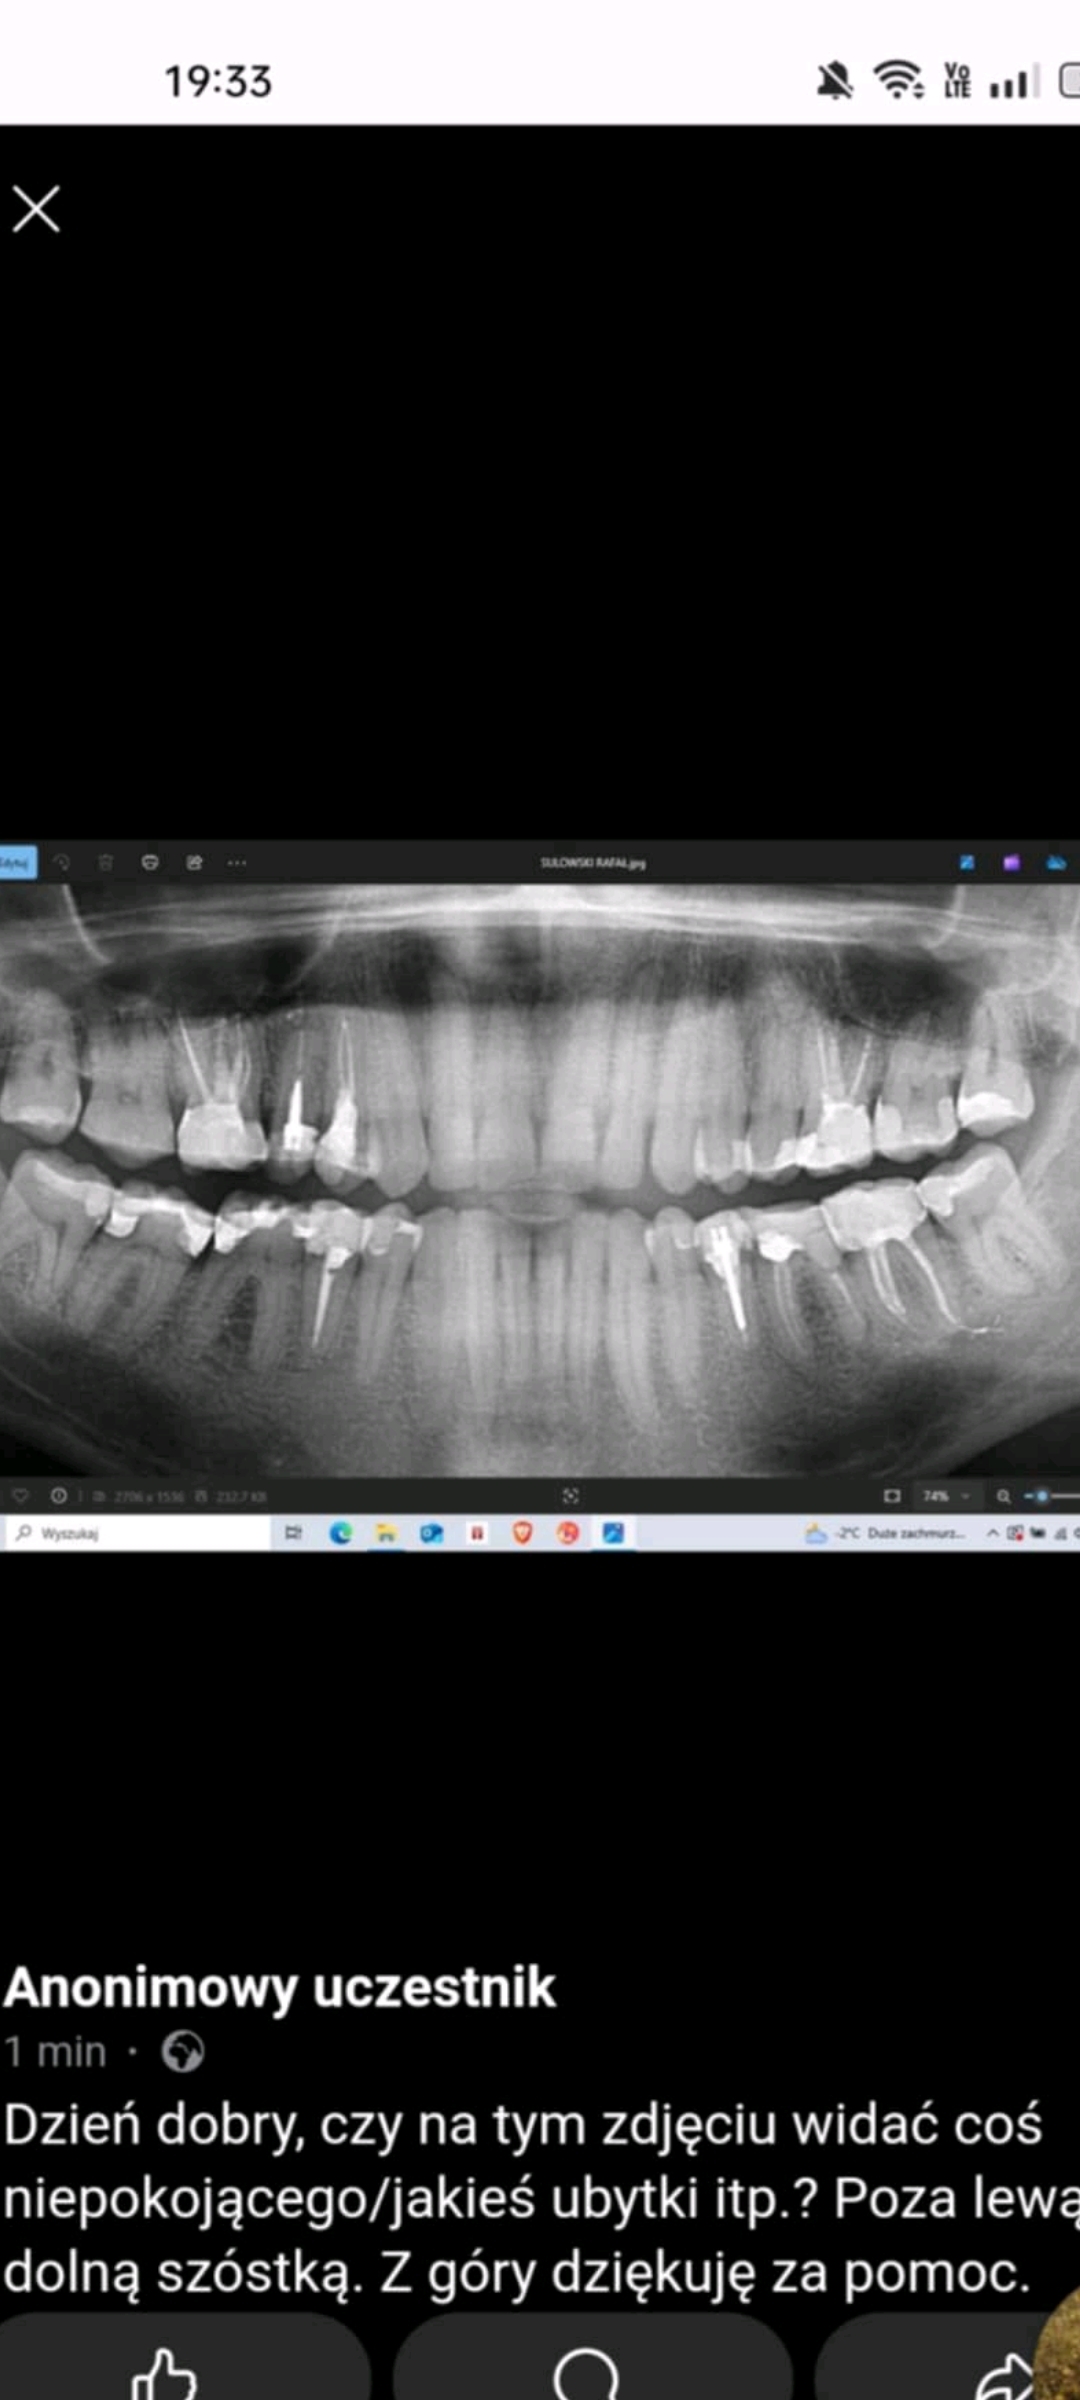

Witam, czy na tym zdjęciu widać cos niepokojącego/jakieś ubytki?

#stomatologia #dentysta #zeby

@ali_baba: a tak ogólnie jak to widzisz, które miejsca mogą być podejrzane?, wiem, że szóstka i siódemka z prawej wyglądają nieciekawie, ale tam było RTG punktowe i jest ok